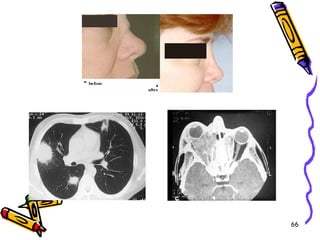

WEGENER

GRANÜLOMATOZİSİ

Üç temel TRİAD:

1- Üst ve/veya alt solunum yollarının

akut nekrotizan granülomu

2- Küçük ve orta büyüklükteki damarları

etkileyen nekrotizan ve granülomatöz

vaskülit

3- Fokal, nekrotizan, kresentik GN

Klinik Gidiş

• Bilateral nodüler ve kaviter lezyonlarla

karakterize pnömonitis (%95)

• Kronik sinüzit (%90)

• Nazofarinkste ülserasyonlar (%75)

• Böbrek tutulumu bulguları (%80)

• Deri döküntüsü, kas ağrısı, polinörit vs.

• Tedavi edilmezse hızlı gidiş, fatal*

• Siklofosfamid ve kortikosteroid ile remisyon,

ancak %50 relaps

66

CHURGE-STRAUSS

SENDROMU

• Alerjik rinit, astm ve eozinofili ile sıkı birliktelik

• Damar lezyonları histolojik olarak PAN ve

mikroskobik polianjiit ile benzer

• Akciğer, kalp, dalak, periferik sinirler ve deri

damarları

• İntra ve ekstravasküler granülomlar, yoğun

eozinofil

• Ciddi renal tutulum nadir

• %70 p-ANCA +